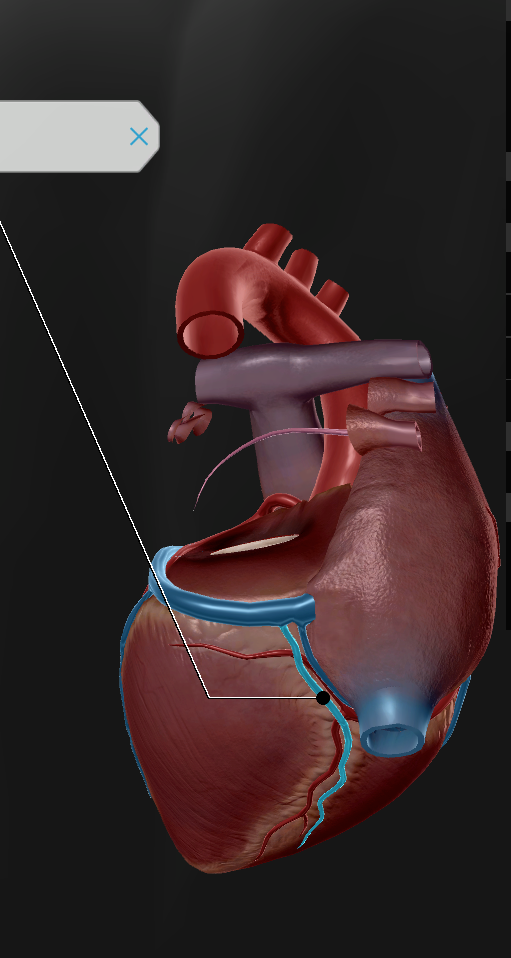

Left Atrium

Right Atrium

Left Ventricle

Right Ventricle

Tricuspid Valve

Bicuspid Valve

Aortic Valve

Papillary Muscle

Pulmonary Valve

Interventricular Septum

Chordae Tendineae